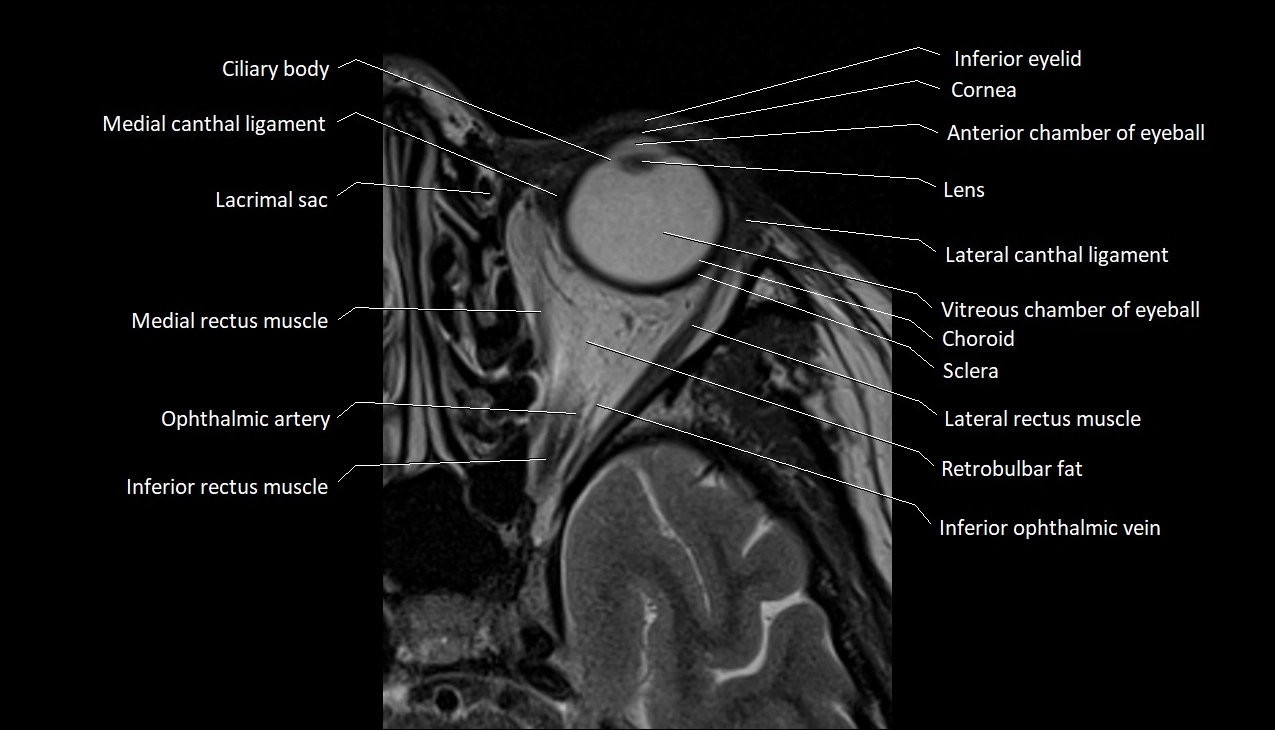

MRI images